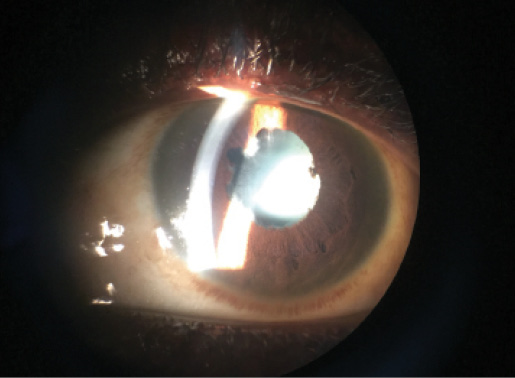

Figure 2. Slit-lamp photograph with an iPhone shows diffuse posterior synechiae and a cataract due to untreated uveitis in an EVD survivor.

Because of resource limitations and lack of eye care providers in many parts of West Africa, many patients have been examined after long-standing ocular inflammation in which structural complications and vision loss have already been observed (Figure 2). In our series of patients in Liberia, nearly 40% of patients showed visual impairment and 60% had developed blindness in their affected eye, underscoring the tremendous impact of vision loss due to uveitis.3